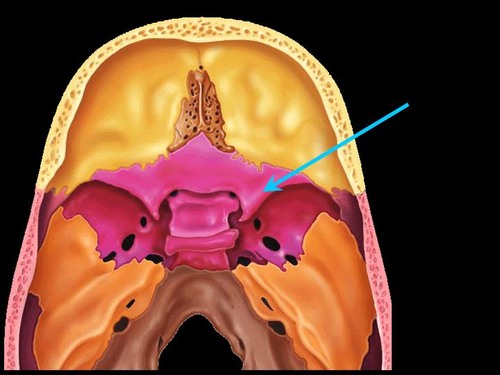

sella turcica

what is the master gland?

pituitary gland

which bone surrounds the master gland?

sphenoid bone